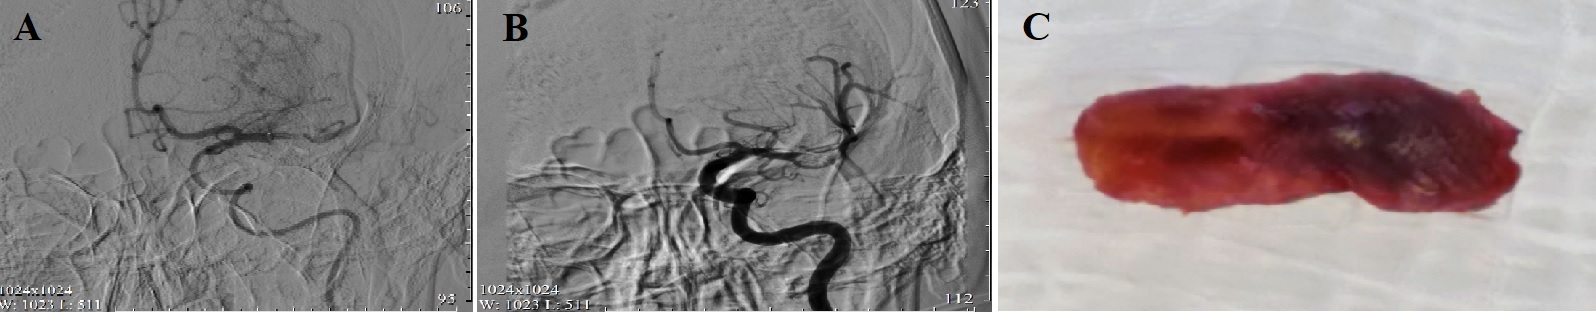

Рисунок 1 - Результаты ангиографии до (А) и после (В) выполнения тромболизиса и тромбоэкстракции: М1 сегмент контрастируется, магистральный кровоток в бассейне левой средней мозговой артерии восстановлен; извлеченный тромб 2х5 мм (С)